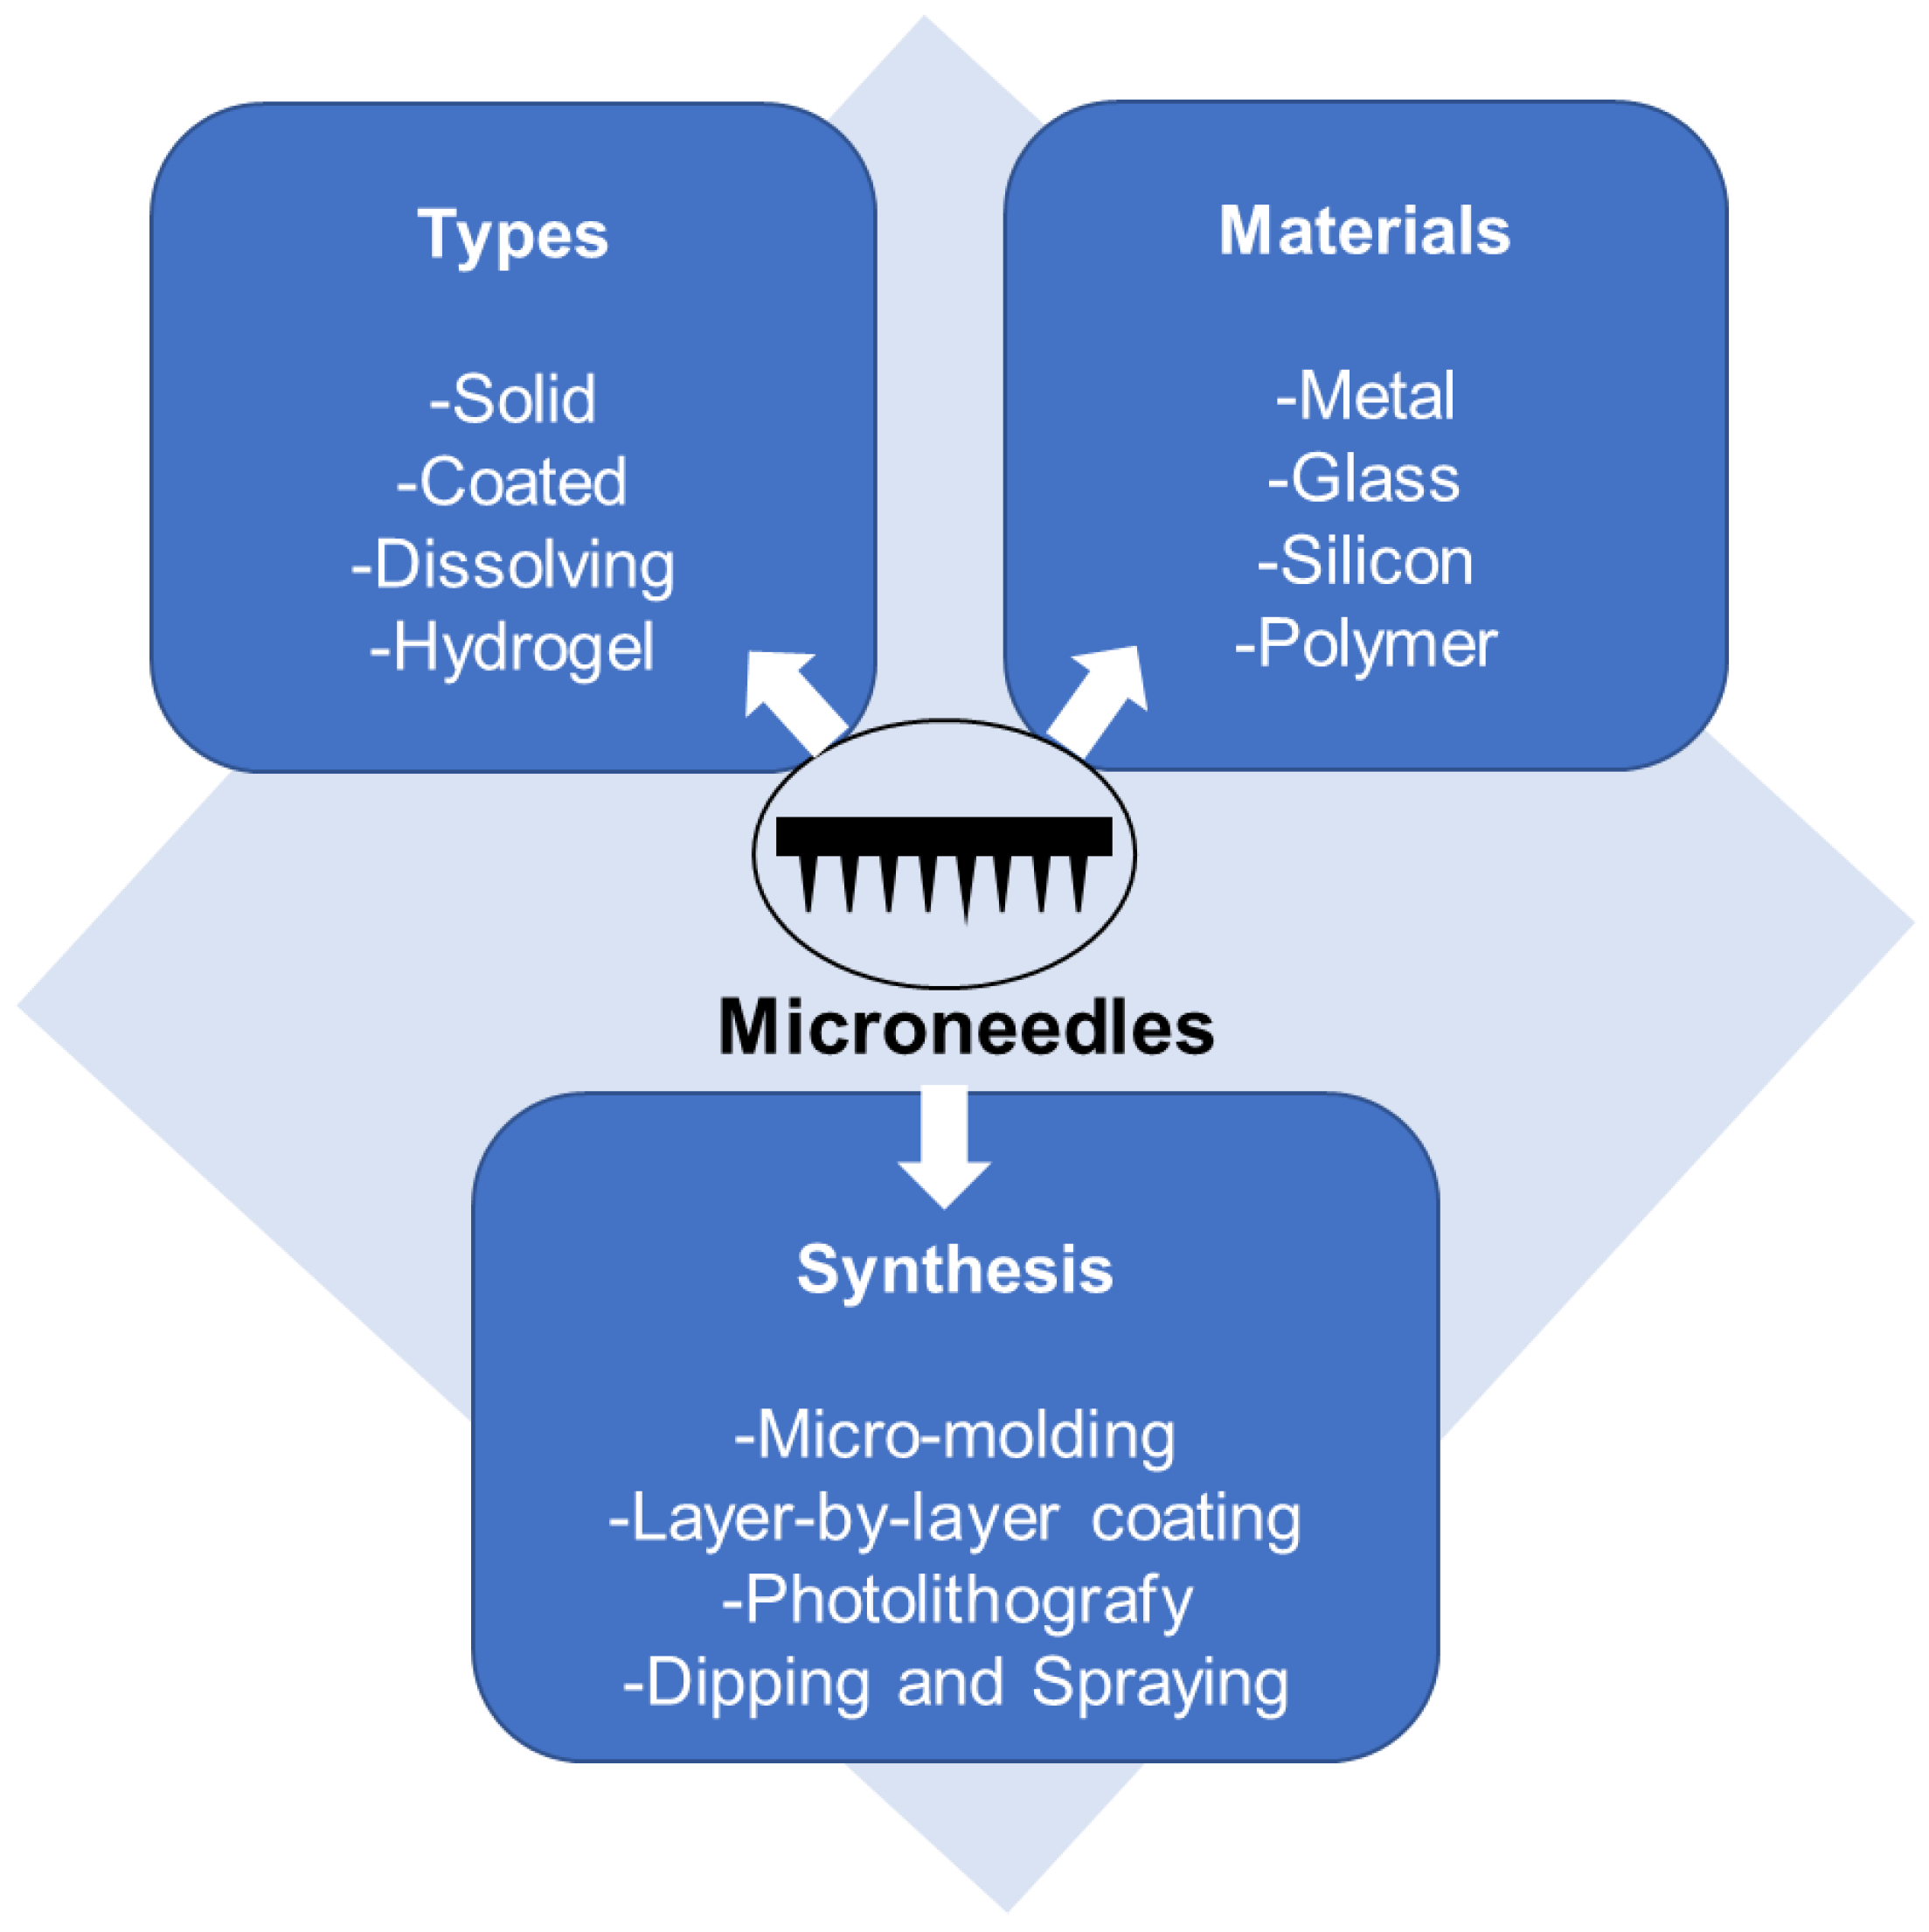

2.3. Microneedles (MNs)

2.3.1. Types of Microneedles Concerning the Technique of Drug Loading and Delivery

2.3.2. Polymeric Microneedles